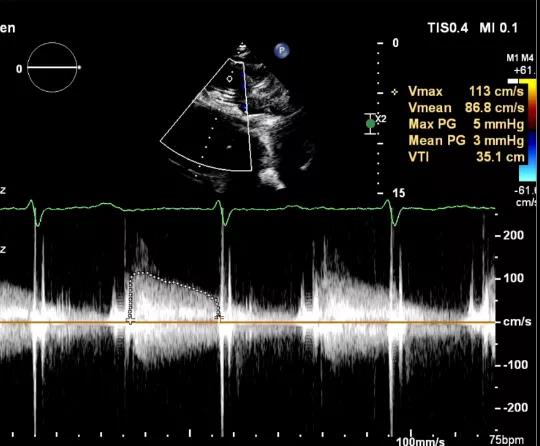

食道超声评估

三尖瓣瓣中瓣术后平均压差3mmHg

术后TV生物瓣活动良好